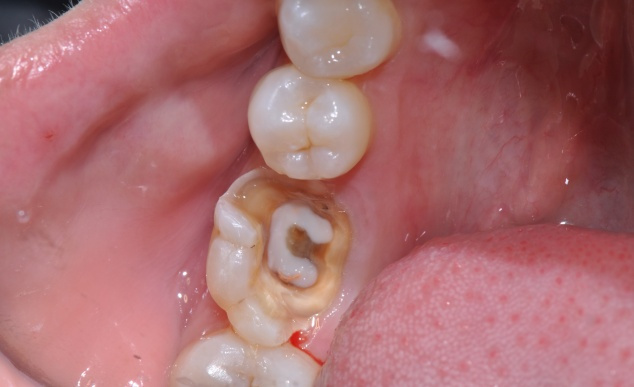

龋齿龋坏的程度怎么分 龋病的形成首先是牙釉质磷灰石晶体的破坏,使得透明而有光泽的釉质变混浊呈现出白垩色斑病变范围逐渐扩大并向深层发展,使牙本质脱钙变软。食物与细菌代谢产生的色素连同牙... 牙齿治疗 朱小溪 1138 2024-03-23

龋病按病变程度怎么分类 龋病是发生在牙体硬组织上慢性、进行性破坏的细菌性疾病。临床表现为牙体硬组织色、形、质各方面发生变化,随着硬组织脱矿和有机物分解的进行,最终牙体组织崩解形成不可自... 牙齿治疗 范姜英杰 914 2024-03-11

龋齿的临床表现是什么 牙齿由三层硬组织及包绕在其中的软组织构成,硬组织共有三种--牙釉质、牙本质及牙骨质。牙釉质是牙齿的最外层半透明的白色硬组织,钙化程度最高、最坚硬,厚2~2.5毫... 牙齿治疗 鲜清怡 591 2024-02-27

龋齿的分类有哪些 按病变深度分类根据病变深度可分为浅龋、中龋和深龋。这一分类方法在临床上最为适用。牙骨质龋多表现为潜掘性龋或表层剥脱,由于牙骨质较薄,尤其是牙颈部,因此病变可很快... 牙齿治疗 吴芳芳 726 2023-11-27